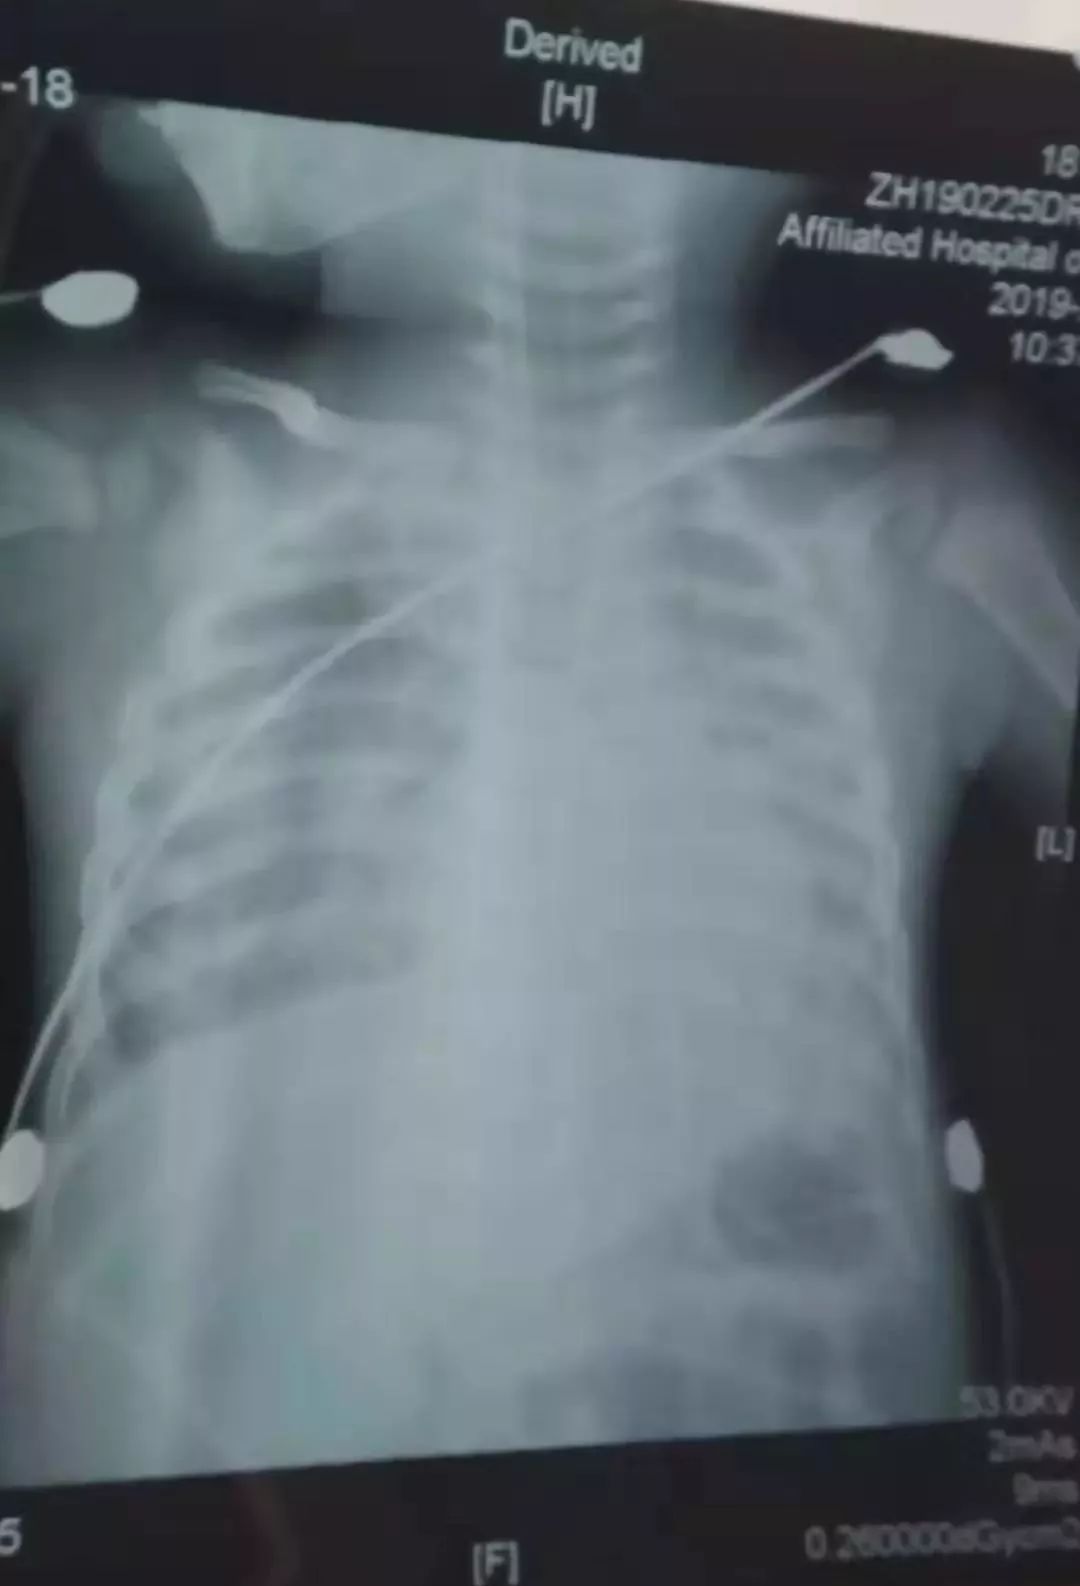

(小睿晞的肺部影像)

2019年01月25日(农历2018年腊月二十),王先生1岁零3个月的儿子小睿晞,住进江苏南通大学附属医院后,被确诊为腺病毒肺炎,治疗十多天后,病情越发严重,农历正月十三,小睿晞被送进了重症监护室。